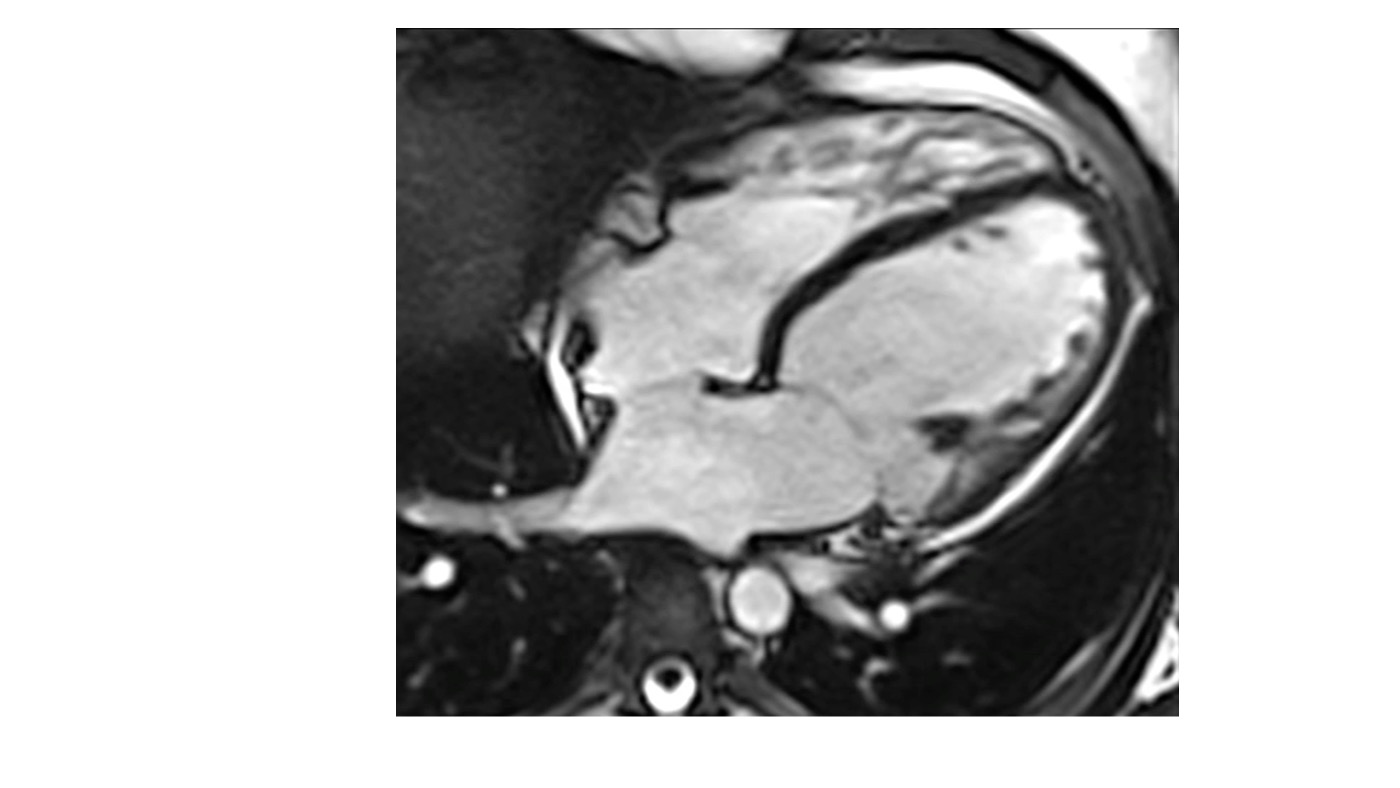

PSIR sequences in the four-chamber view demonstrated extensive subepicardial late gadolinium enhancement involving the lateral wall of the left ventricle.